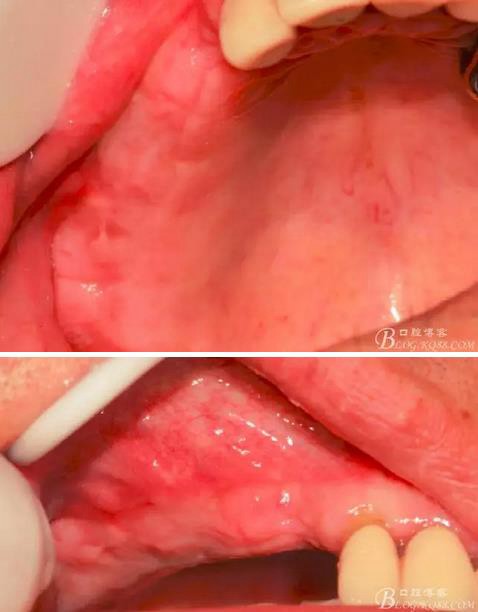

術后10天口內(nèi)照。

術后40天口內(nèi)照。